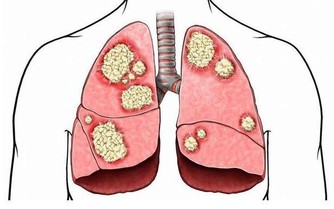

二、心梗

心梗被稱為“迅捷的殺手”,患者常常在很短時間內,就被奪去了生命。

其實,雖然心梗從發作到猝死只有短短幾分鐘,但很多患者在心梗發病前,是有一些預警症狀的,

這些症狀往往會持續一兩天,如果在這時候儘早干預,就能有很大概率挽救生命。